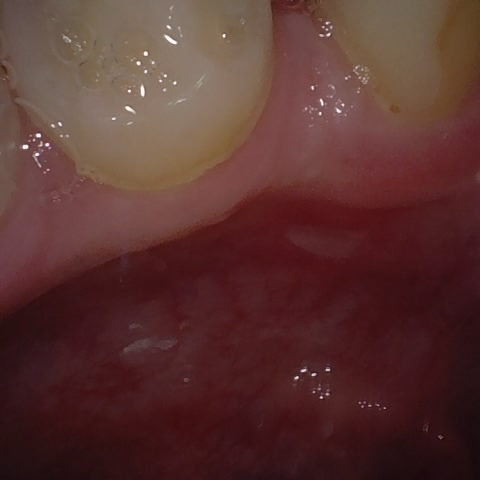

Annotated as "Good"